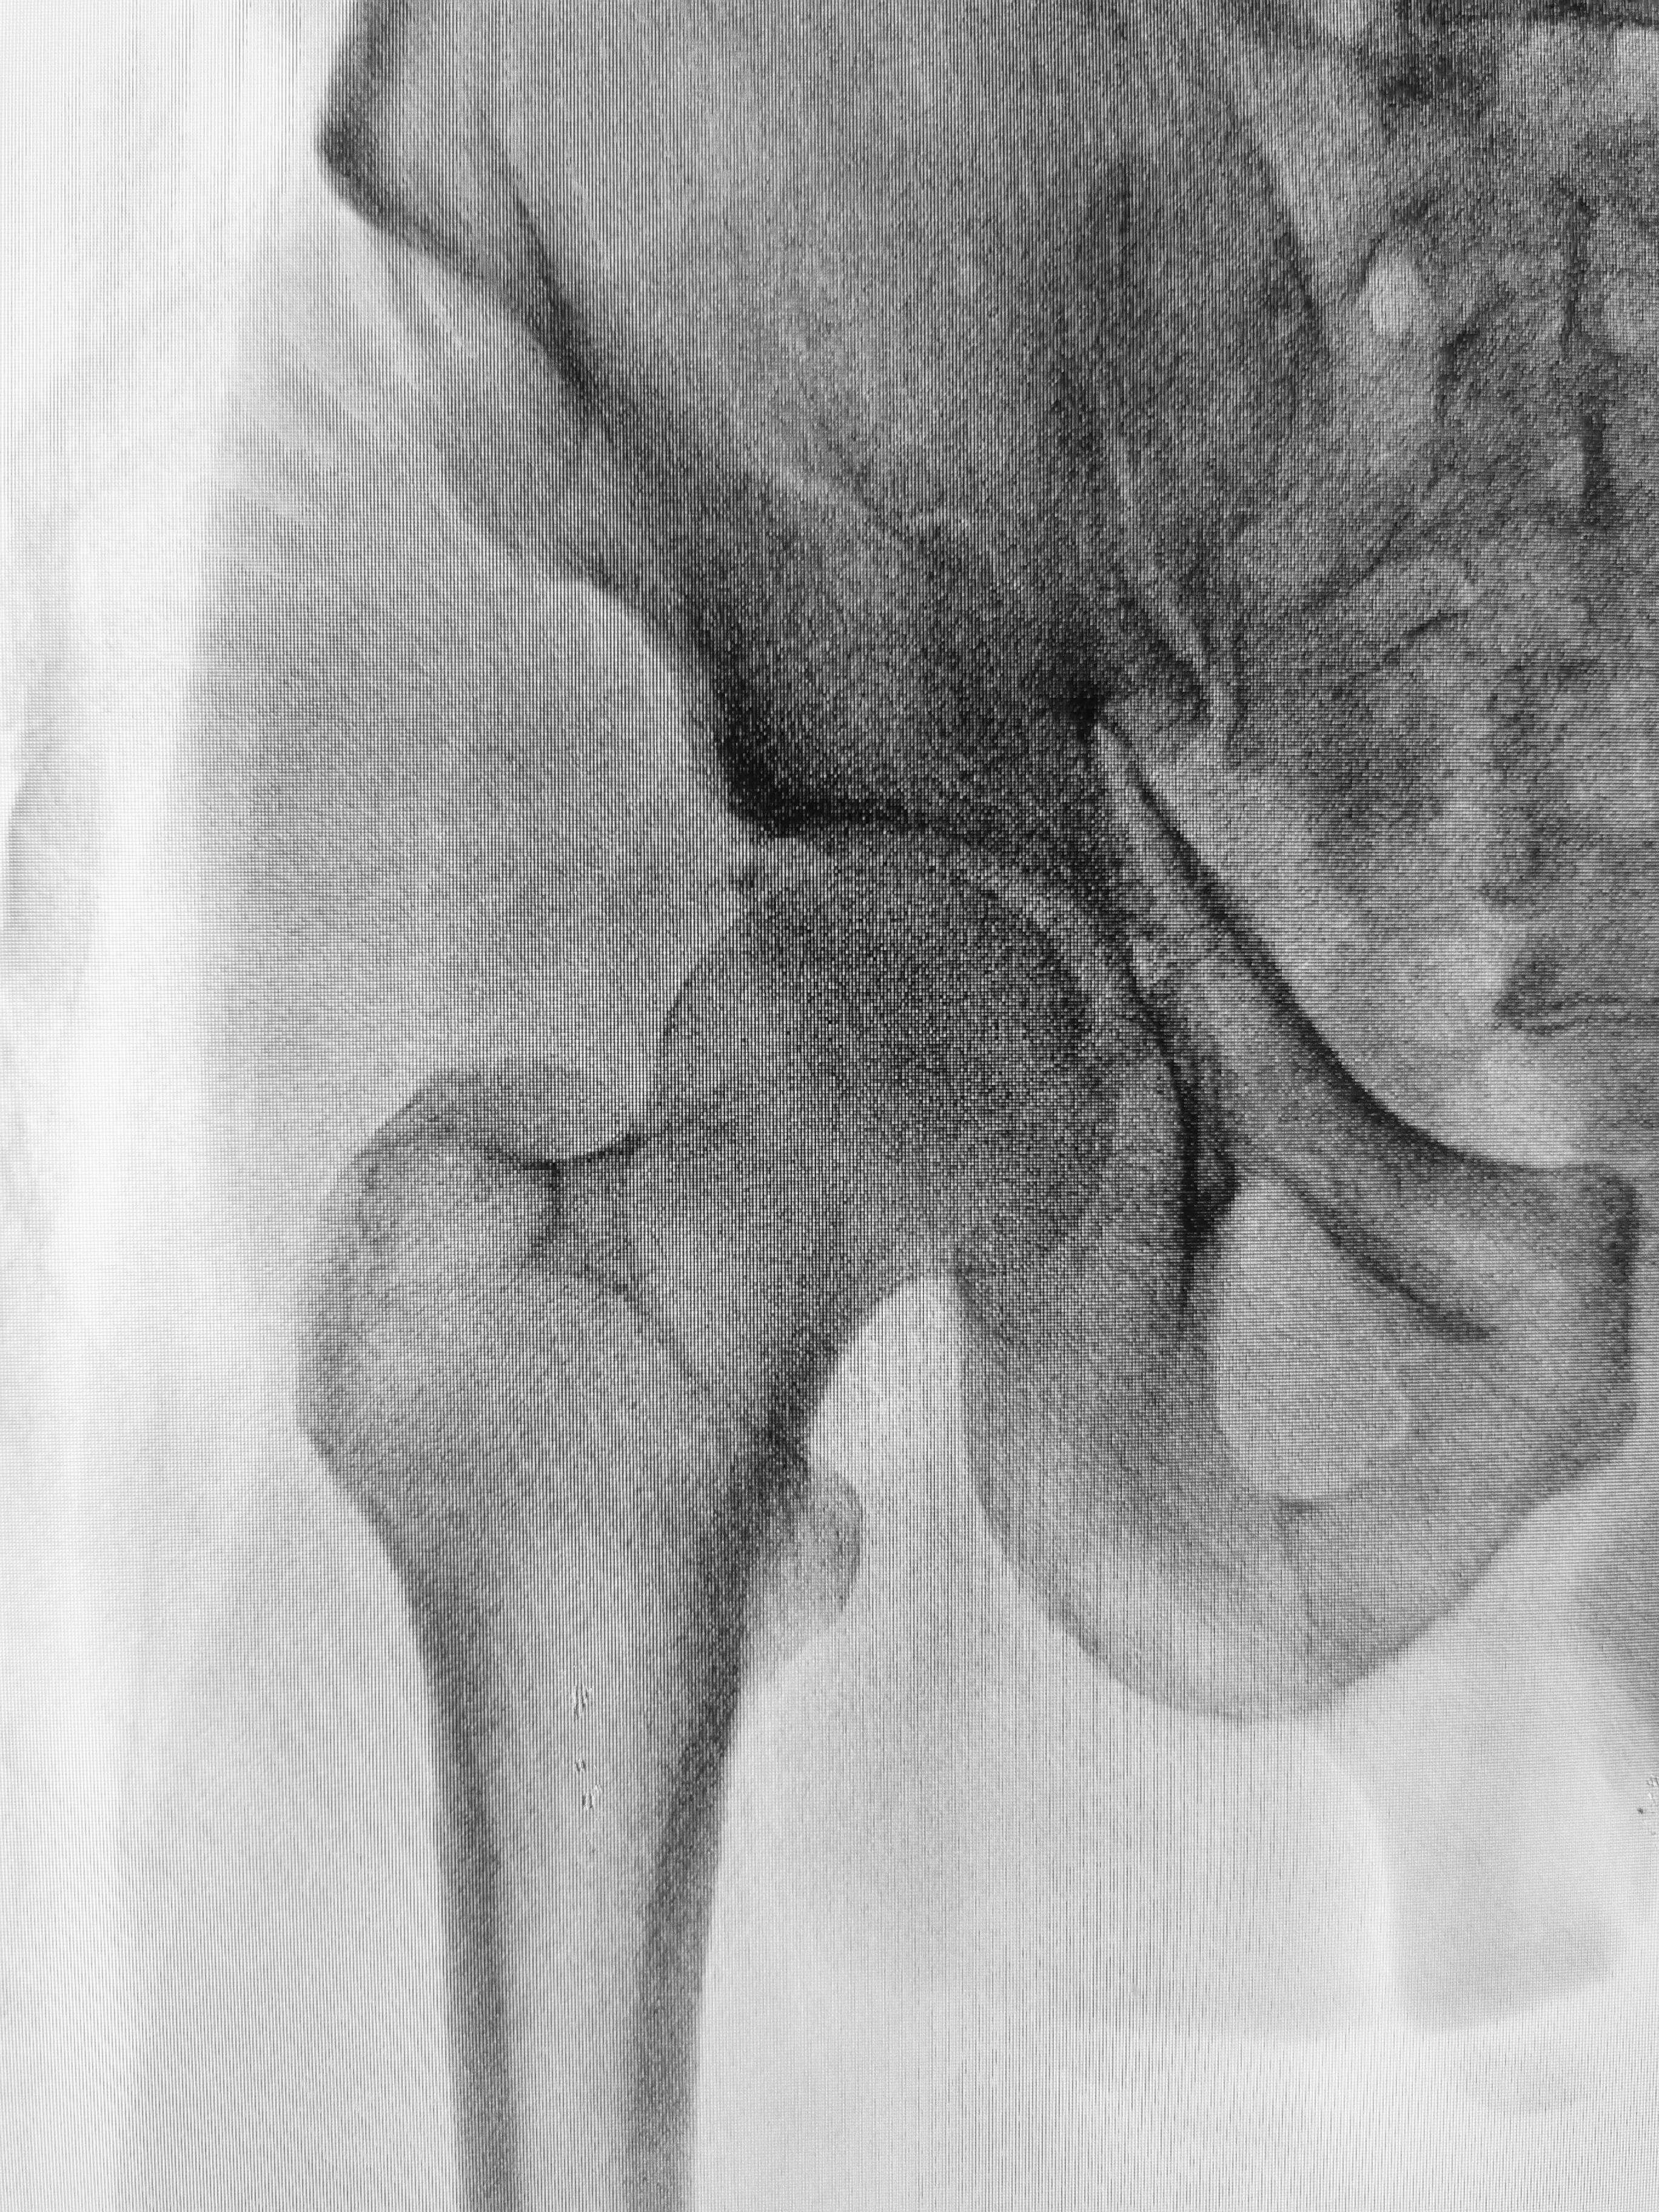

10. Fluoride and Hip Fractures in the Elderly

According to studies, fluoride may increase hip fractures in the elderly.

High doses of fluoride (average 26 mg per day) were used in trials to treat patients with osteoporosis in an effort to harden their bones and reduce fracture rates. This treatment actually led to a higher number of fractures, particularly hip fractures (Inkovaara 1975; Gerster 1983; Dambacher 1986; O’Duffy 1986; Hedlund 1989; Bayley 1990; Gutteridge 1990. 2002; Orcel 1990; Riggs 1990 and Schnitzler 1990).

One Chinese study looked at hip fractures in six Chinese villages, and found an increase in hip fractures as the concentration of fluoride rose from 1 ppm to 8 ppm (Li 2001).